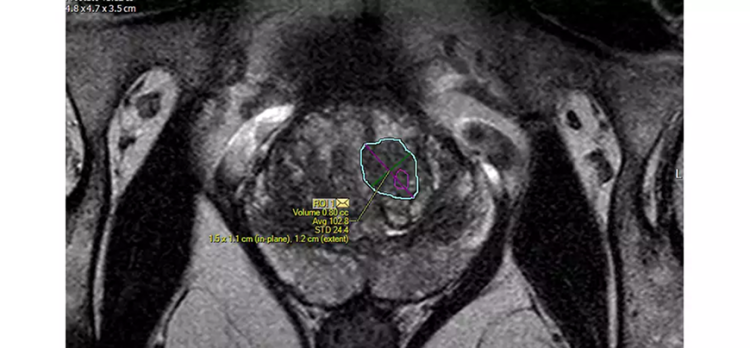

您可以减少前列腺的手动轮廓:DynaCAD Prostate 基于模型的腺体分割会自动执行腺体的 3D 分割。您可以更改或调整所有三个平面中的分割结果。由此产生的分割报告了总体腺体体积,并为 UroNav MR/US 引导的融合活检程序奠定了基础。

用户生成的 ROI 可以显示在前列腺的 3D 模型以及研究中的多个图像序列上。